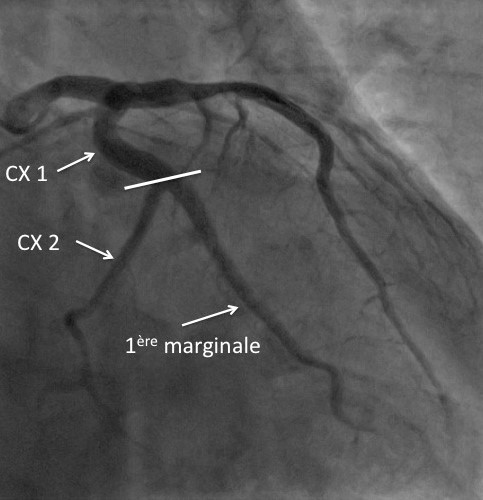

Il est admis que la plaque vulnérable a un cœur lipidique riche avec une chape fibreuse épaisse et se localise le plus souvent au niveau des segments proximaux des principales artères épicardiques.

La plaque à risque de rupture : le prototype de la plaque à risque de rupture contient un large cœur nécrotique très riche en lipide avec une chape fibreuse fine (≤65µm) et inflammatoire. Ce sont généralement des plaques de grande taille, avec un remodelage positif marqué (phénomène de Glagov), limitant l’obstruction vasculaire (plaque moyennement obstructive à l’angiographie). D’autres caractéristiques sont décrites telles que une néovascularisation, des calcifications irrégulières et une inflammation adventitielle. (3)